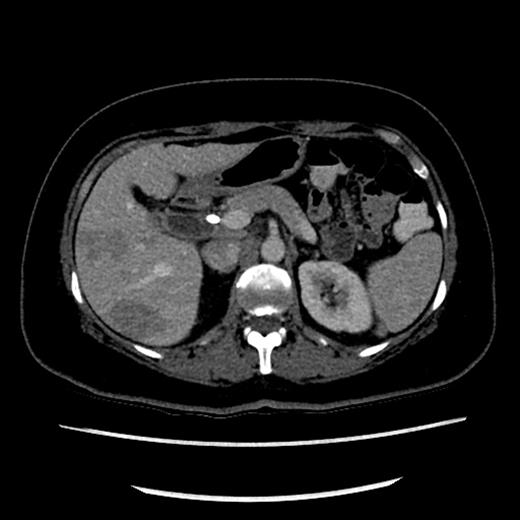

The liver function tests revealed an obstructive picture. Bilirubin level was 86 µmol/l (normal 2–24 µmol/l). Gamma glutamyl transferase (GGT) and alkaline phosphatase were 347 and 340 U/l, respectively. In view of prior history of choledocolithiasis, an ERCP was undertaken. An eccentric stricture at the level of the junction of cystic duct and CBD was seen along with a dilatation of proximal the bile duct. There were no ductal calculi. A plastic stent was inserted to relieve the jaundice (Fig. 1). These findings raised the suspicion of a malignant process, and a computerized tomography (CT) scan of the chest, abdomen and pelvis was consequently performed.

The CT scan revealed multiple hypodense liver lesions predominantly in the right lobe of the liver (Segment 6 and 8) highly suspicious of metastatic deposits (Fig. 2). A preliminary diagnosis of metastatic cholangiocarcinoma was made on this basis.

CT scan showing hypodense lesions in the liver with CBD stent in situ.